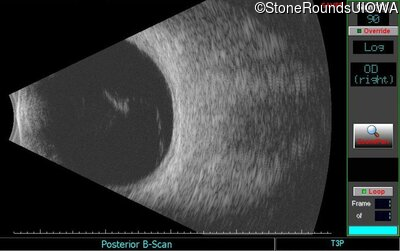

B-Scan Ultrasonography - Right - Count Fingers 2'

Exemplar